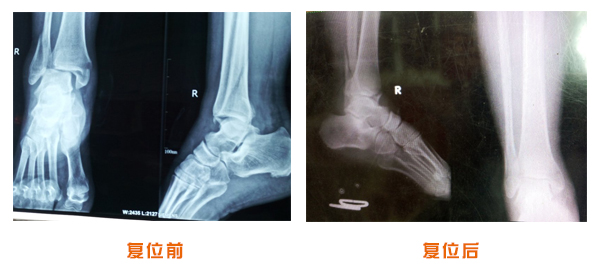

肥城市安駕莊梁氏骨科醫院是一所以梁氏手法正骨配合膏藥為特色的現代化專科醫院。

梁氏骨科術始創于清雍正年間,歷經八代,至今已有三百年歷史。據1929年泰安縣志載“梁瑞圖先生,字增生,號蓮峰,安駕莊人,精岐黃并發明接骨,凡跌打車凡跌打車軋皮不破而碎骨者......【詳細】 |